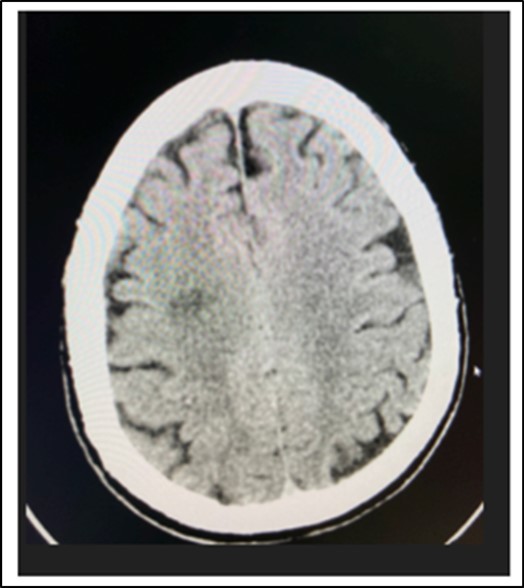

At the emergency room of the tertiary hospital, the patient had persistence of the diplopia and dizziness. The initial impression at that time was Cerebrovascular Infarct, thus a Plain Cranial CT Scan was done (conducted 6 hours after the onset of symptoms), which revealed a hypodense focus in the sub-cortical region of the right centrum semiovale extending to the right corona radiata, orbits, midbrain and pons were all normal. (Figure 2 and Figure 3)

Figure 4.Cranial CT Scan plain, axial of the patient done 6 hours after onset of diplopia, shows a hypodense focus in the sub cortical region of the right centrum semiovale extending to the right corona radiata